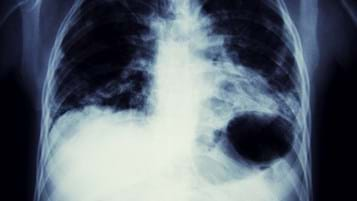

Asbestos-related lung cancer

In this guide we will answer frequently asked questions about asbestos-related lung cancer.